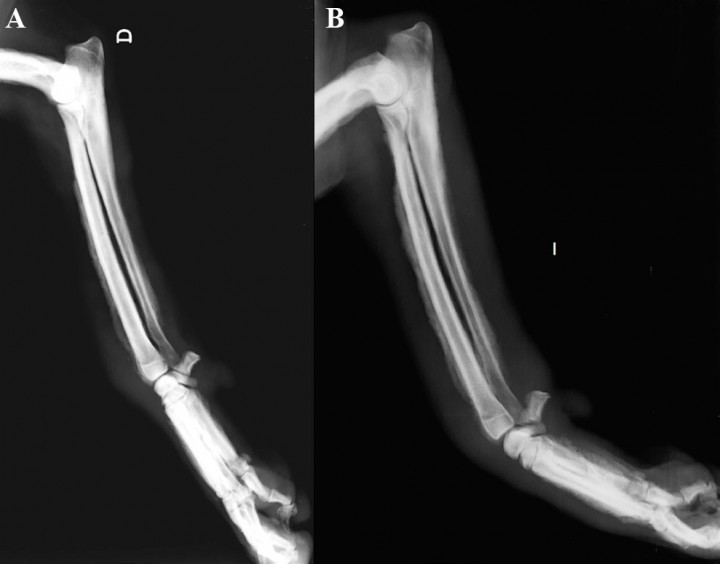

Se presenta un perro macho castrado de 5 años, Griffon Azul de Gascuña de 22 kg de peso. Acude a consulta por una cojera con inflamación de la extremidad anterior izquierda de 1 semana de evolución. En la exploración se observa dolor a la palpación de las extremidades anteriores con zonas de inflamación, sobre todo del tercio distal de las mismas. Las extremidades posteriores presentan también inflamación de la zona tarsal de forma más leve. Las alteraciones analíticas encontradas son neutrofilia leve (11,94 K/μl; valor de referencia: 2,95-11,64 K/μl), monocitosis (2,61 K/μl; valor de referencia: 0,16-1,12 K/μl), incremento de la ALP (296 U/l; valor de referencia: 23-212 U/l) e hiperglobulinemia (4,7 g/dl; valor de referencia: 2,5-4,5 g/dl). Se realizan radiografías digitales simples con proyecciones dorsopalmares (Fig. 1) y mediolaterales (Fig. 2) de extremidad anterior derecha e izquierda y proyecciones mediolaterales de la extremidad posterior derecha e izquierda (Fig. 3).

<p>Proyección mediolateral de cúbito y radio. <strong>(A) </strong>Derecha. <strong>(B) </strong>Izquierda.</p>

Proyección mediolateral de cúbito y radio. (A) Derecha. (B) Izquierda.

<p>Mismas radiografías de la Figura 2. Se observa reacción perióstica del tipo en empalizada (ver flechas) con afectación del aspecto dorsal y palmar del cuerpo de los huesos metacarpianos y del proceso accesorio del carpo, de la cara craneal de la epífisis distal y de la diáfisis del radio, del borde caudal de la diáfisis distal del cúbito y del margen craneal y caudal del tercio distal del húmero. No hay afectación de las superficies articulares ni destrucción ósea. Se aprecia la tumefacción de los tejidos blandos.</p>

Mismas radiografías de la Figura 2. Se observa reacción perióstica del tipo en empalizada (ver flechas) con afectación del aspecto dorsal y palmar del cuerpo de los huesos metacarpianos y del proceso accesorio del carpo, de la cara craneal de la epífisis distal y de la diáfisis del radio, del borde caudal de la diáfisis distal del cúbito y del margen craneal y caudal del tercio distal del húmero. No hay afectación de las superficies articulares ni destrucción ósea. Se aprecia la tumefacción de los tejidos blandos.